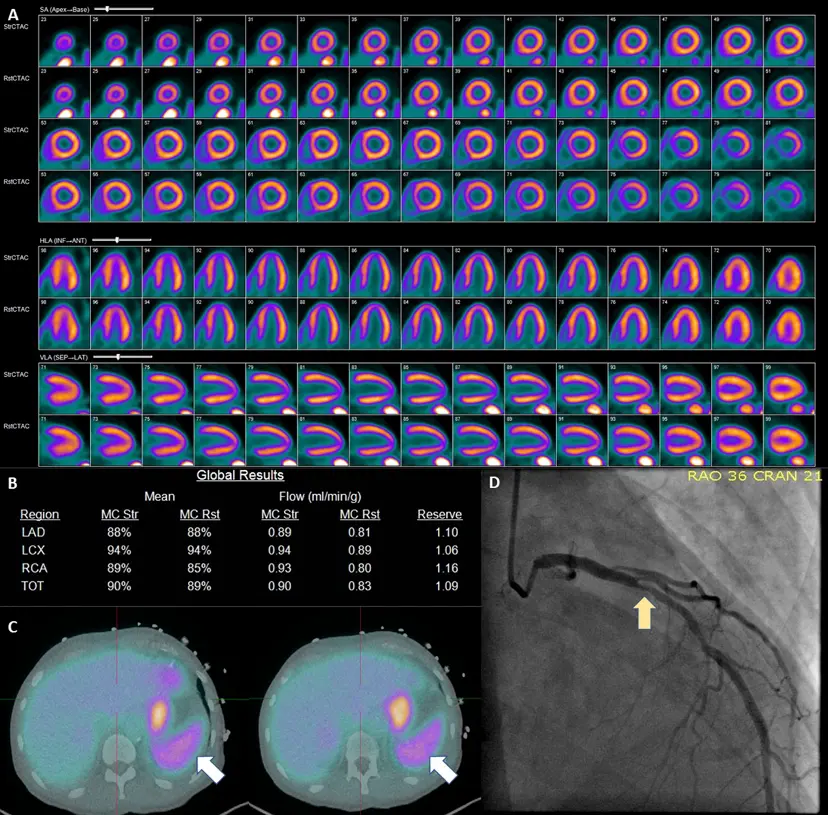

Example of Splenic Shutoff without Perfusion Defects

57-year-old male with hypertension, diabetes mellitus, and chronic kidney disease who presented for the evaluation for suspected CAD. A PET-MPI imaging revealed normal relative regional with no identifiable perfusion defects. (B) However, albeit a normal resting myocardial blood flows, the patient’s stress myocardial blood flow remained unchanged following the administration of regadenoson with a severely reduced myocardial flow reserve of 1.09. Assessing the patient’s hemodynamic responses, we can also note an unchanged heart rate (75 bpm rest vs 76 bpm stress) and failure to observe expected EF enhancement (36% at rest vs 37% at stress). The patient’s coronary artery calcium score (6246) only served to increase the concern for CAD. (C) Inspection of the spleen (white arrows) reveals a failure to exhibit visual signs of splenic switch-off (SRR was 1.1). Based on these findings, the patient was recommended to obtain an invasive catheterization due to growing suspicion of non-response to regadenoson. D ICA revealed a significant obstructive coronary artery disease LAD (Left Anterior Descending) lesion (yellow arrow) 1